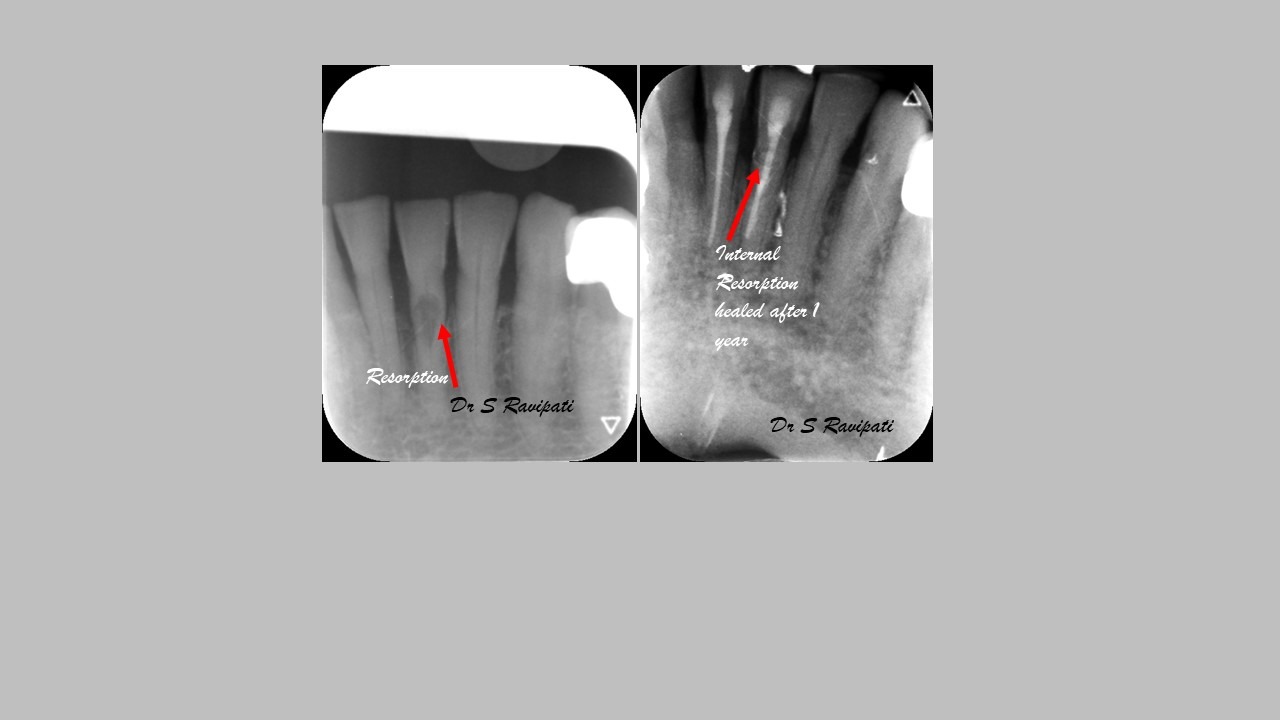

Pathological changes occur in the tooth due to trauma or caries progression which can, in turn, cause bacteria to invade the root canal system.

The main goal of endodontic therapy is to remove necrotic pulp tissues, to eliminate or significantly reduce microorganisms and their toxic products from the canals and also to prevent inflammatory lesion in the periapical area. Endodontic therapy protects the tooth from further invasion from microorganisms. If the tooth is left without treating, the infection may spread and cause pain and swelling.

Studies have shown thorough cleaning with instruments, disinfection and sealing the canals contribute to the successful healing of the infection and this success is reported as 95%.